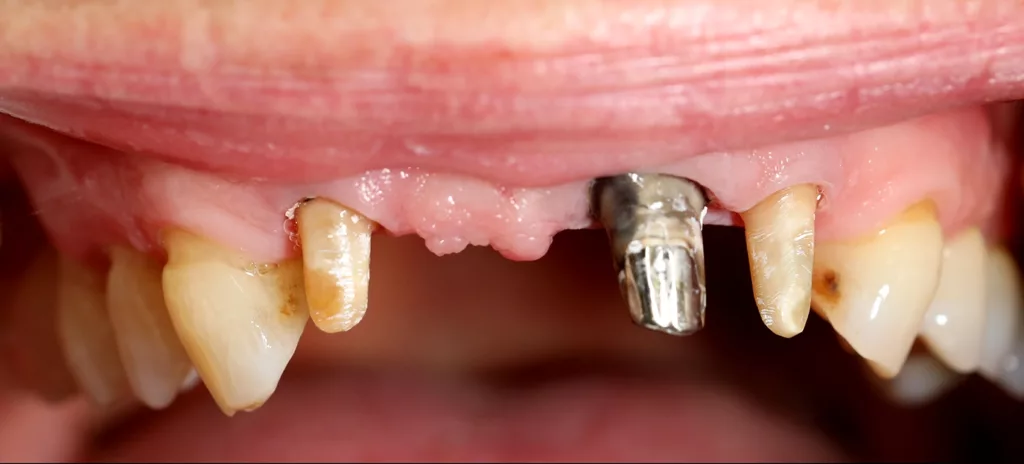

Die Brücke wurde in der ersten Behandlungssitzung unter lokaler Anästhesie geschlitzt und abgehebelt. Der Pfeilerzahn 21 präsentierte sich daraufhin stark verfärbt und mit einem metallischen Stift-Stumpf-Aufbau (Abb. 3). Nach minimaler Nachpräparation im zervikalen Bereich und Reinigung der Stümpfe wurde die Situation im Oberkiefer und der Gegenkiefer abgeformt sowie der habituelle Biss registriert. Als Grundzahnfarbe wurde A2 bestimmt.